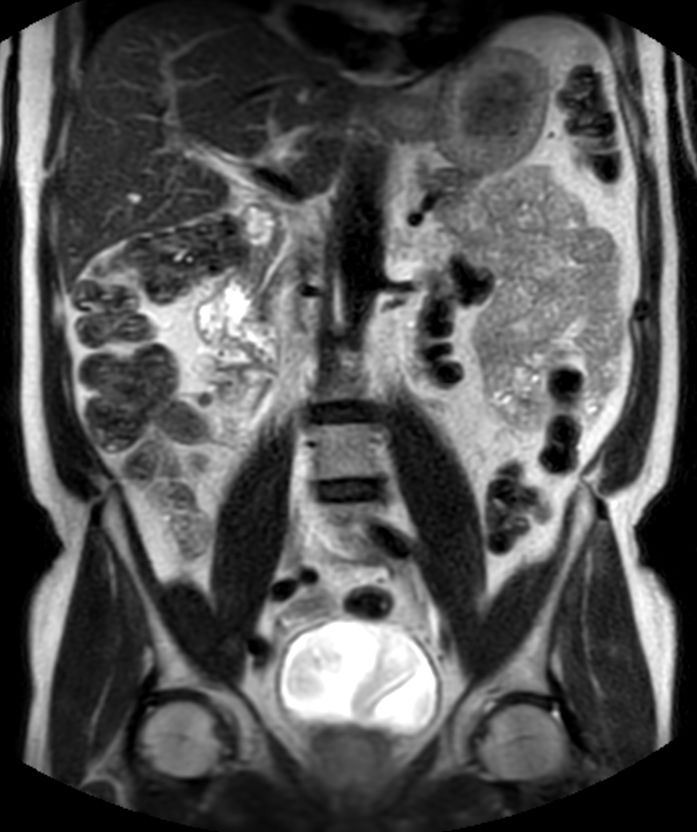

Coronal T2w TSE (2 stations)Dual coil